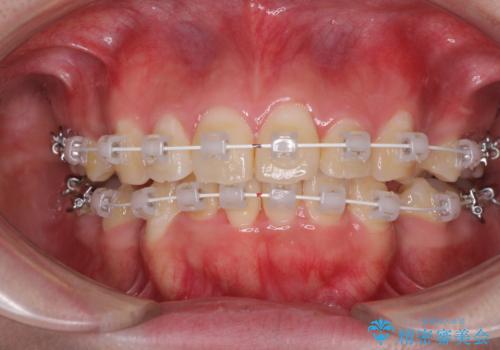

前歯の出っ歯と口の閉じにくさを抜歯矯正で改善 目立たないワイヤー矯正

- 矯正装置

- 審美装置

- 1年10ヶ月

4本の歯を抜歯したことで、飛び出していた口元が引っ込み、横顔が大きく改善されました。

咬み合わせが悪化することのないようにスペースを閉じていくことができ、比較的スムーズに治療を進めることができました。